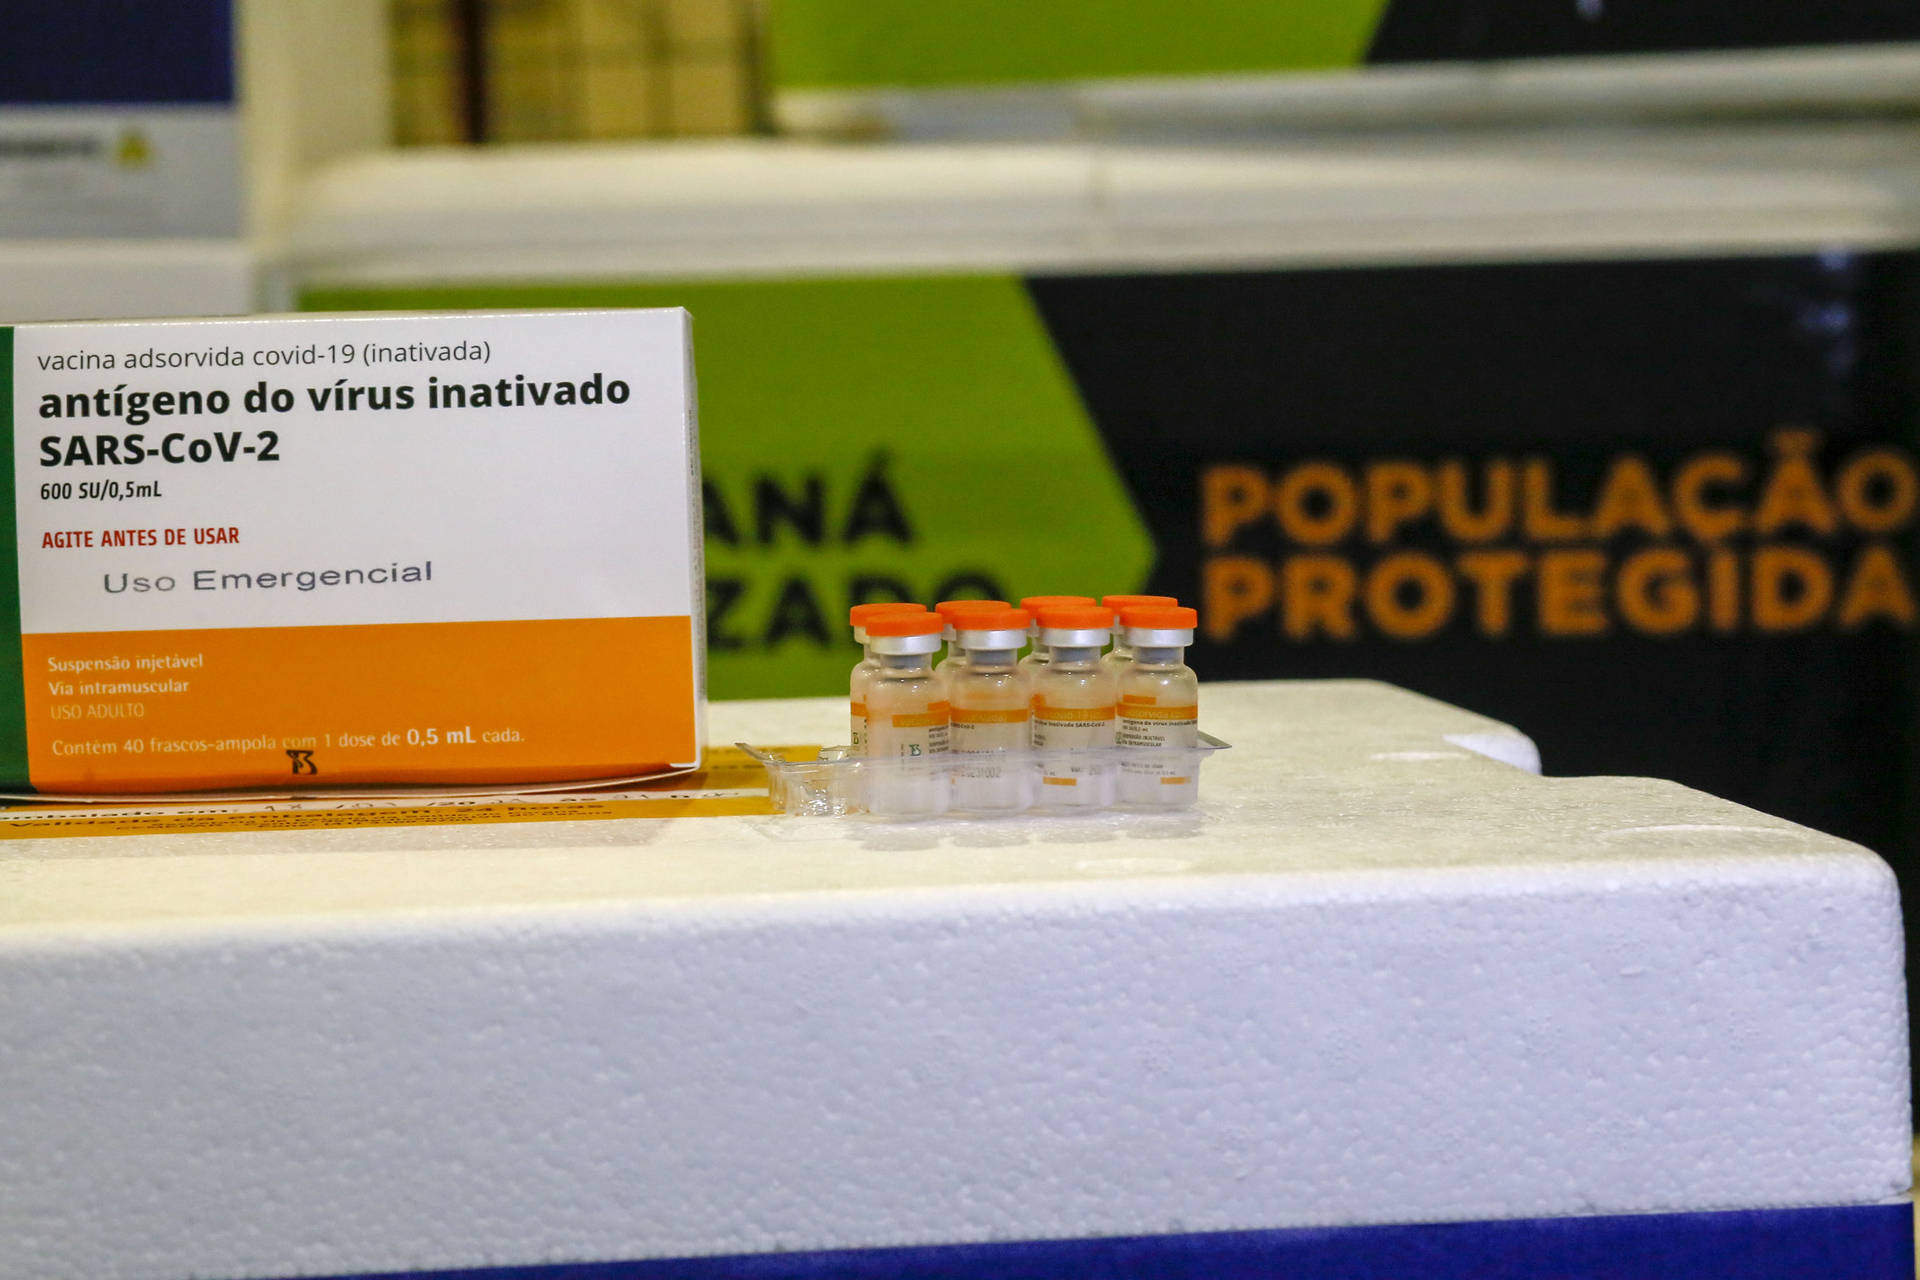

- Coronavírus no Paraná